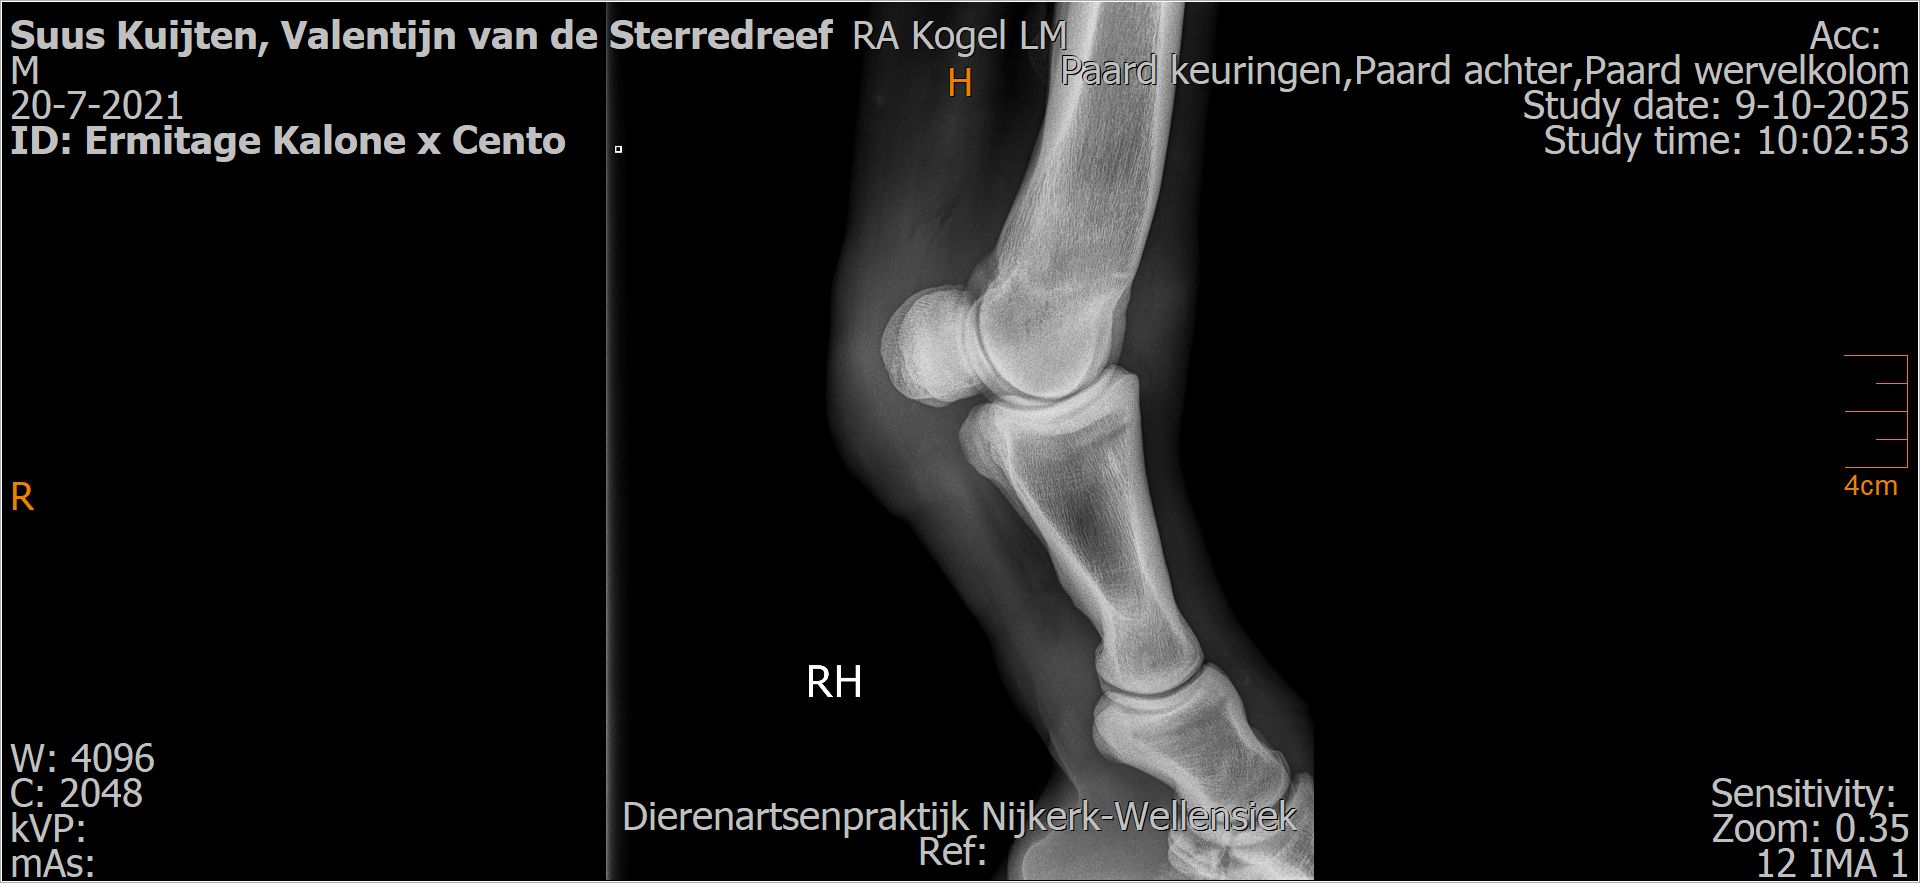

Valentijn van de Sterredreef

Leeftijd:

4

Röntgenfoto’s